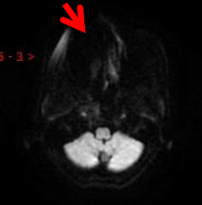

由于种植牙已固定在牙槽骨上或黏合在相应的连接物上,具有很高的牢固度,通常在3.0T(含) 以下场强的MRI设备中不会发生移动和变形,所以不用担心你的牙齿会被吸飞了哦,但在牙科植入物所在的部位可能会出现一些伪影。 像下图这样:

但是如有可拆卸的假牙或者金属牙箍,建议MRI检查时取下,不然影像可能会和下面图像一样,黑乎乎的一片,什么都看不见,这种情况就要影响诊断了。